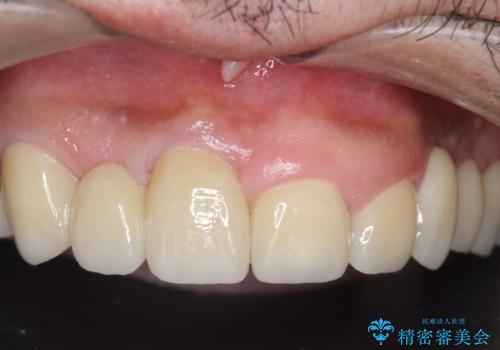

オールセラミッククラウン ブリッジによる欠損歯の補綴

- 歯がない左側でものが咬めず、右側で咬むと歯が痛むので診て欲しいといらっしゃった方の症例です。

根尖病変が認められる歯は再根管治療を行い、歯根が破折していた左上4は抜歯しました。

インプラントは希望されなかったため、左側は1番から7番のロングスパンブリッジによる補綴を行いました。

今回用いたオールセラミッククラウンは、ジルコニアフレームという白い素材の上にセラミックを盛っているため審美性が非常に高いのが特徴です。

またジルコニアは人工ダイヤモンドの材料にも使われているほど高い強度を持っており、そのためオールセラミッククラウンは審美性だけでなく、奥歯やブリッジの補綴も可能とするクラウンです。